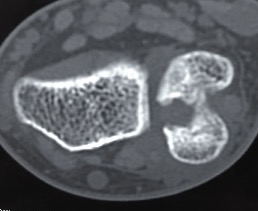

DRUJ Replacement